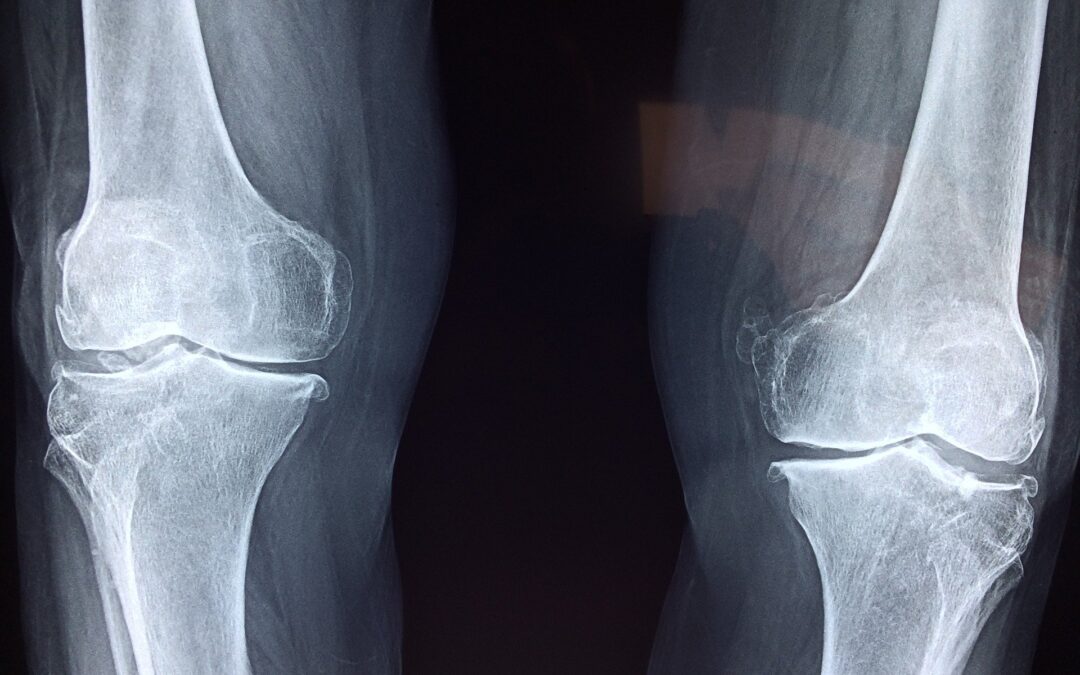

So, you’ve been told that you will need a knee replacement. While researching other options, you hear about a treatment that involves knee injections. That treatment is called Viscosupplementation. Viscosupplementation involves injecting a substance called...